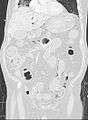

Pneumatosis intestinalis at computed tomography in intestinal ischemia. Lung window for better representation of the gas deposits in the intestinal walls. Coronal reconstruction.

Pneumatosis intestinalis in the coronal computed tomography in lung window. It can be seen next to gas entrapment in the bowel wall and gas in the stomach wall and in numerous vessels, including the portal vein into the liver.